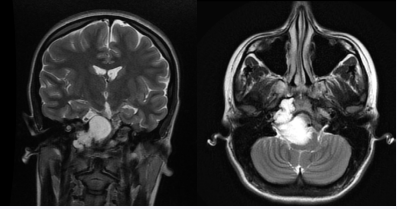

Pituitary adenomas are the most common cause of sellar and parasellar mass, comprising about 10 to 15% of all intracranial tumors. Despite histologically benign, they have the capacity to invade adjacent structures, such as: sphenoidal sinus, cavernous sinus, skull base or nasopharynx. The clivus invasion is rare and basisphenoid is the most commonly affected portion [9]. Ectopic pituitary adenomas are extremely unusual and arise from residual cells along the migration tract of the anterior portion of the pituitary gland, during passage from Rathke’s pouch to the sellaturcica. Ectopic locations include the suprasellar region, sphenoid sinus, cavernous sinus and clivus. In these cases pituitary gland is commonly normal. However, purely ectopic clival pituitary adenomas are exceedingly rare. Pituitary adenomas classically present with bitemporal hemianopsia, however ectopic adenomas usually do not, unless they involve the optic chiasm. Headache is a common complain, but it is unspecific and cannot distinguish a pituitary adenoma from other lesions. Invasive and ectopic pituitary adenomas can manifest as a clival neoplasm in the imaging study and lead to misdiagnosis [10-12]. CT-scan typically reveals an enhancing soft-tissue mass that shows bone destruction. On T1-weighted MRI, pituitary adenomas demonstrate an isointense to slightly hypointense mass that enhances after administration of contrast (Figure 1).

Figure 1 Coronal and sagittal T1-weighted images revealing a giant pituitary adenoma.

Figure 1: Coronal and sagittal T1-weighted images revealing a giant pituitary adenoma.

On T2-weighted images, they range from isointense to hyperintense, unless they contain intratumoral hemorrhage or cystic changes [13].